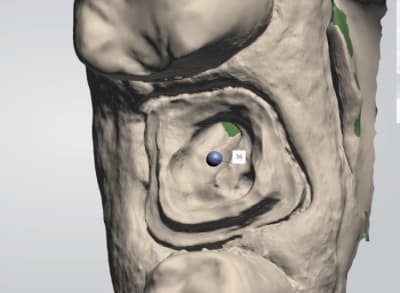

chicot29

26/02/2018 à 21h02

Vue platre.

T'en as rien a branler de la couleur. le protho travaille sur le platre.